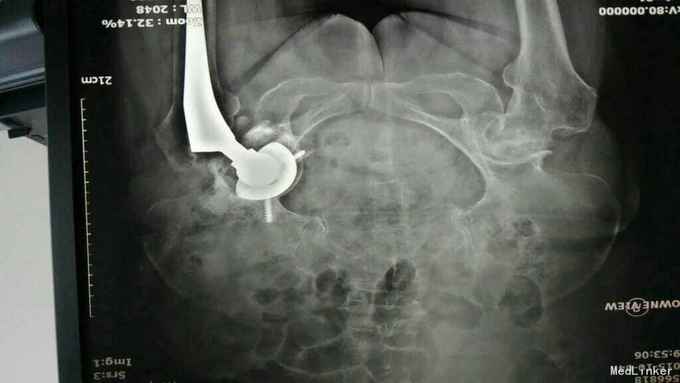

主诉:左髋关节置换术后疼痛活动受限3年 病史:3年前患者因左股骨颈骨折在当地县医院就诊,诊断明确后行全髋关节置换术,术前正常出院。出院后即感左髋关节疼痛不适,活动疼痛加重,休息缓解,疼痛位于腹股沟明显。反复于当地医院及成都等医院就诊,诊断不明确,考虑有金属过敏可能。4天前患者疼痛加重,活动进一步受限,无关节红肿,无肿胀,无畏寒发热,无其他关节疼痛。为进一步治疗收入我科。 患病以来。精神食欲可,体力下降。

查体:轮椅推入,左髋关节后外侧见10cm手术切口瘢痕,双侧腹股沟压痛,双侧大转子叩痛,双髋关节活动受限,4字实验(+),双下肢肌力3级。左乱关节屈曲90度,旋转不能。左下肢纵向叩痛(+)。 辅助检查:彩超示脂肪肝。x线腰椎骨质疏松,压缩性骨折。ESR 38,CRP 12。 影像学如下:

诊断:左髋关节置换术后假体松动; 右侧股骨头缺血坏死; 重度骨质疏松症 高血压病 压缩性骨折 治疗:左髋关节翻修术。(植骨、钛网骨水泥杯,骨水泥柄或翻修长柄MP(Link))